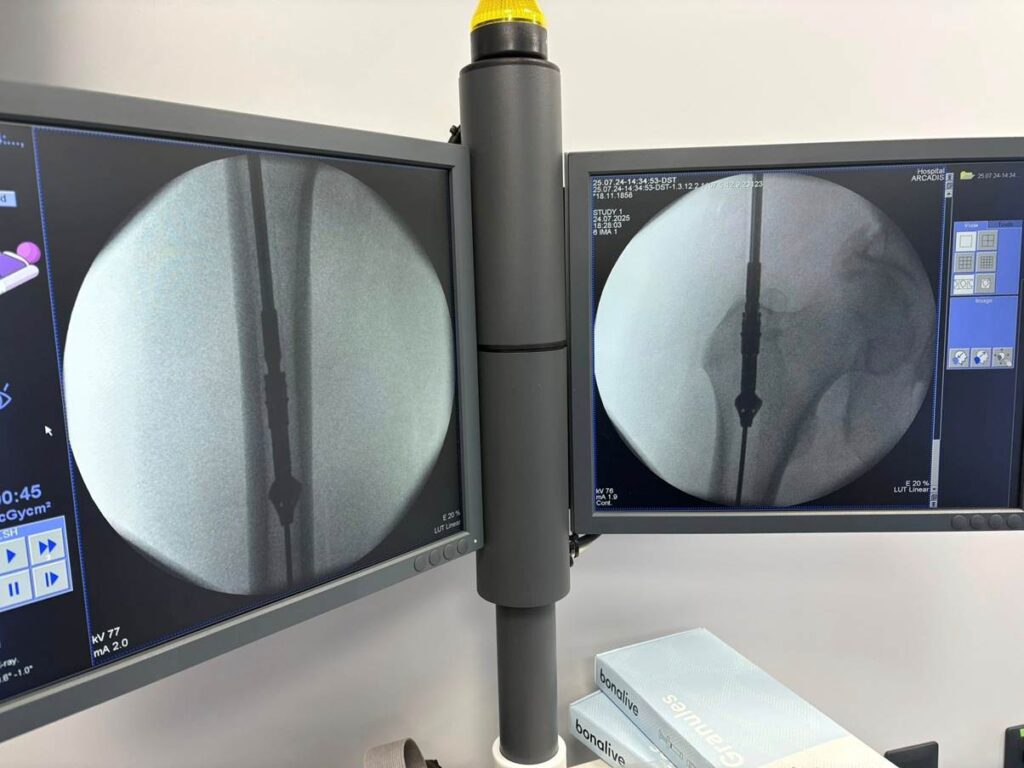

Поэтому сначала выполнили только фиксацию из малых доступов. И взяли ткани «на посев». Сеяли и на аэробные, и на анаэробные бактерии.

Никакого роста. Всё стерильно.

Поэтому следующим этапом мы (доктора Долгош Д.В., Никитин П.В., Парий В.Б. и ваш покорный слуга) взяли 12 см малоберцовой кости (свободный трансплантат) и кортикальную кость из бедра пациента с помощью RIA-2. Как раз этот этап на фото. Черно-белом, чтобы Фейсбук меньше возмущался. Там в фильтре-боксе как раз костная крошка из бедра видна. А она, как вы понимаете, красного цвета . Всё это перемешали еще и с BONALIVE (заменителем кости нового поколения с антибактериальным эффектом) и имплантировали. С ещё одной дополнительной пластиной.